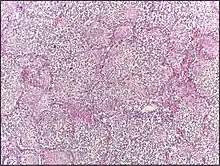

صورة مجهرية لإصابة بذات الرئة الفصي.